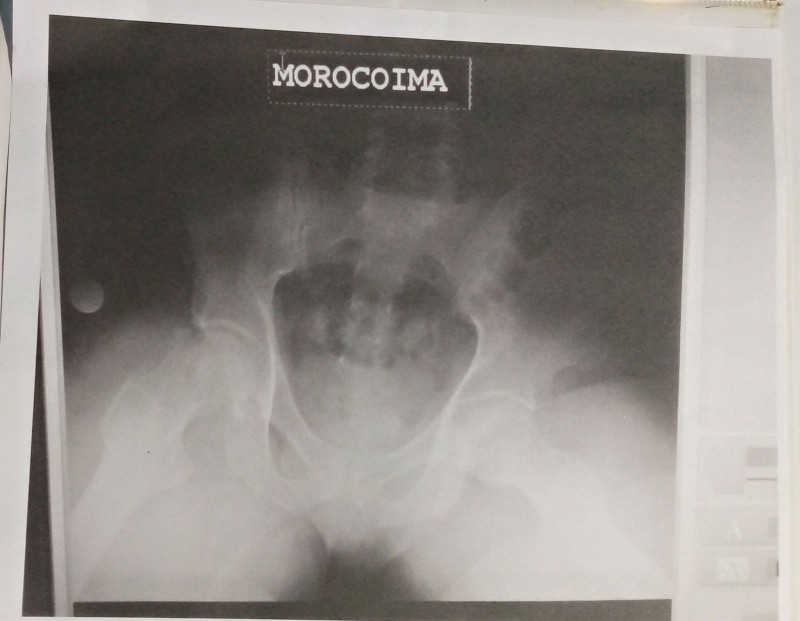

Un cordial saludo de parte de jorvin Morocoima venezolano 29 años me dirijo a ustedes para solicitar una ayuda de suma importancia me diagnosticaron necrosis vascular cadera bilateral debo ser operado requiero prótesis total d cadera no cementada ceramica polietileno de doble movilidad estos material tiene un costo de 4400$ y soy de escasos recursos económicos x tal motivo acudo confiando en su solidaridad q mi Dios me los bendiga sin más agregar mi agradecimiento de antemano su colaboración atentamente jorvin Morocoima